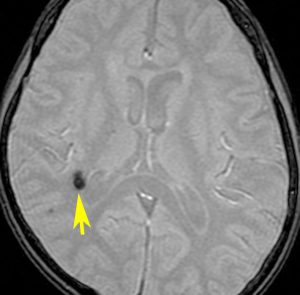

海綿状血管腫 微小血管障害

多発性微小脳出血

- ほとんどが小児に生じるものです

- 放射線治療を受けた患者の40%くらいでみられます

- 照射後10年くらい長期観察をしていると実際に非常に高頻度にみます

- 海綿状血管腫は,放射線誘発2次腫瘍というよりも,放射線による脳内小血管損傷による血管障害として捉えた方がよいです

- T2スターというMRI画像で発見できます

11歳の時に全脳室照射24グレイ・12分割を受けた女の子です。10年以上経過して,脳のあちこちに小さな黒い点状のものが見えるようになってきました。これは子供の頃に放射線治療を受けた人に多く,なんでもないもので症状は出ませんし,ほっておいていいものです。微小な脳静脈の放射線損傷による血液の漏れだと考えられています。

- 低信号(黒いシミみたいなもの)として脳内たくさん見られることがあります

- これは血液の中の鉄分が脳に滲み込んだ形跡をみているものです

- だから,海綿状血管腫とは言わないで,blood leak(血液が漏れた痕跡)と読んだ方がいいものです

- 海綿状血管腫というと腫瘍みたいだからです

- 年月の経過とともに数が増加します

- 海綿状血管腫は発生しても何ら症状を呈することはありません

- 治療をせずに放置します

- まれに小さな脳出血を生じますが,経過を見れば血腫は自然に吸収されます